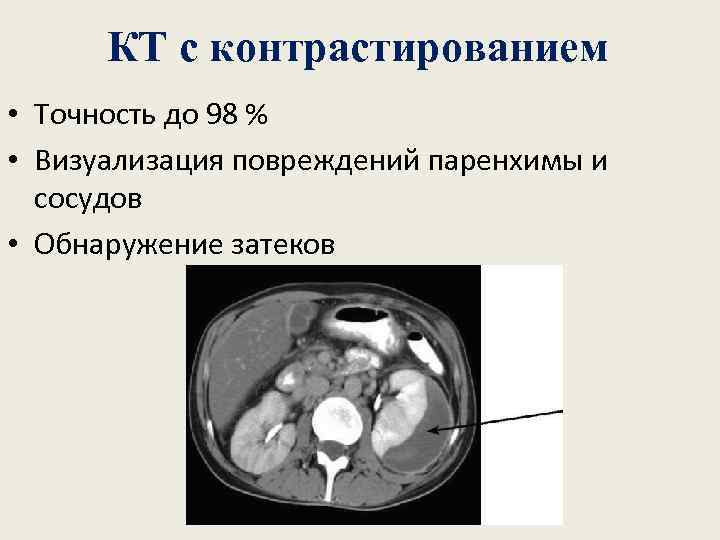

КТ с контрастированием • Точность до 98 % • Визуализация повреждений паренхимы и сосудов • Обнаружение затеков